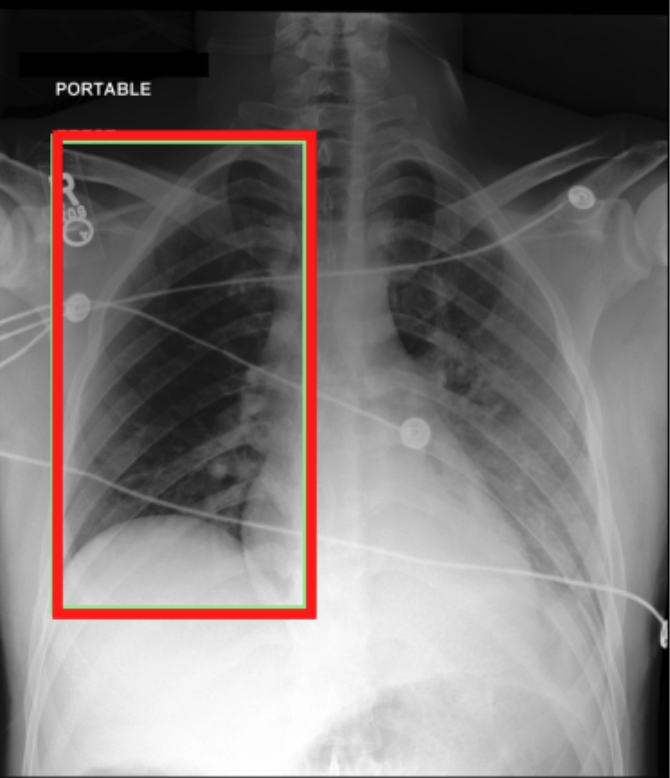

4.3.3 Visual grounding

In this section, we evaluate RadVLM’s visual grounding capabilities, which could help clinicians localize specific regions or pathologies on a CXR. This is particularly useful once a pathology has already been identified – either by a radiologist’s input or through our previously described AI tasks – since it allows one to pinpoint exactly where the abnormality appears on the image.

We report performance metrics for the three main grounding tasks RadVLM was trained on: anatomical grounding using the Chest Imagenome test set, abnormality grounding using the VinDr-CXR test set, and phrase grounding using the MS-CXR test set (Table 1). For each task, we use mean Average Precision (mAP) as our primary evaluation metric.

Our results show that RadVLM performs well at localizing anatomical regions (e.g., “right lung”, “aortic arch”, illustrated in Figure 5a), achieving a mAP of 85.8 %, by far surpassing the other CXR grounding models (Table 4). This advantage is partly explained by including the Chest Imagenome dataset (and thus the anatomical grounding task) in the training set, which CheXagent and MAIRA-2 did not leverage. However, it remains a key feature for any grounding model to possess a fine-grained understanding of CXR anatomy.

For the abnormality grounding task, RadVLM is less consistent (Figure 5b), likely due to higher sparsity of abnormality locations and labels, yet it still achieves best performance (Table 4). For the phrase grounding task, while MAIRA-2 and CheXagent demonstrate great performance, RadVLM surpasses them with a mAP of 81.8% (Table 4), presumably benefiting from the newly released PadChest-GR dataset (Castro et al.,, 2024) used for training.

Overall, these results show that our instruction tuning strategy for visual grounding (covering three essential tasks), combined to a modern VLM backbone, offers a promising avenue to help clinicians localize anatomical and pathological features during a CXR exam. Furthermore, providing fine-grained details within an LLM-generated output may also enhance the ability to answer grounded questions in a multi-turn setting, as we explore next.